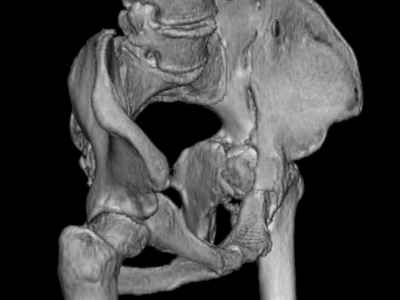

Уважаемые коллеги, возник вопрос по лечению нашей пациентки 60 лет. Около года назад множественная травма: в том числе Т-образный перелом вертлужной впадины.

На сегодняшний день сращение отломков имеется на ограниченных участках, имеется дефект задней колонны вертлужной впадины. Движения неплохие, ходит с костылями, приступая на ногу.

По мнению эдопротезистов при установке антипротрузионного кольца или октопуса не хватит костного материала и необходимо перед протезированием выполнить реконструкцию впадины, иначе чашка протеза неминуемо выпадет.